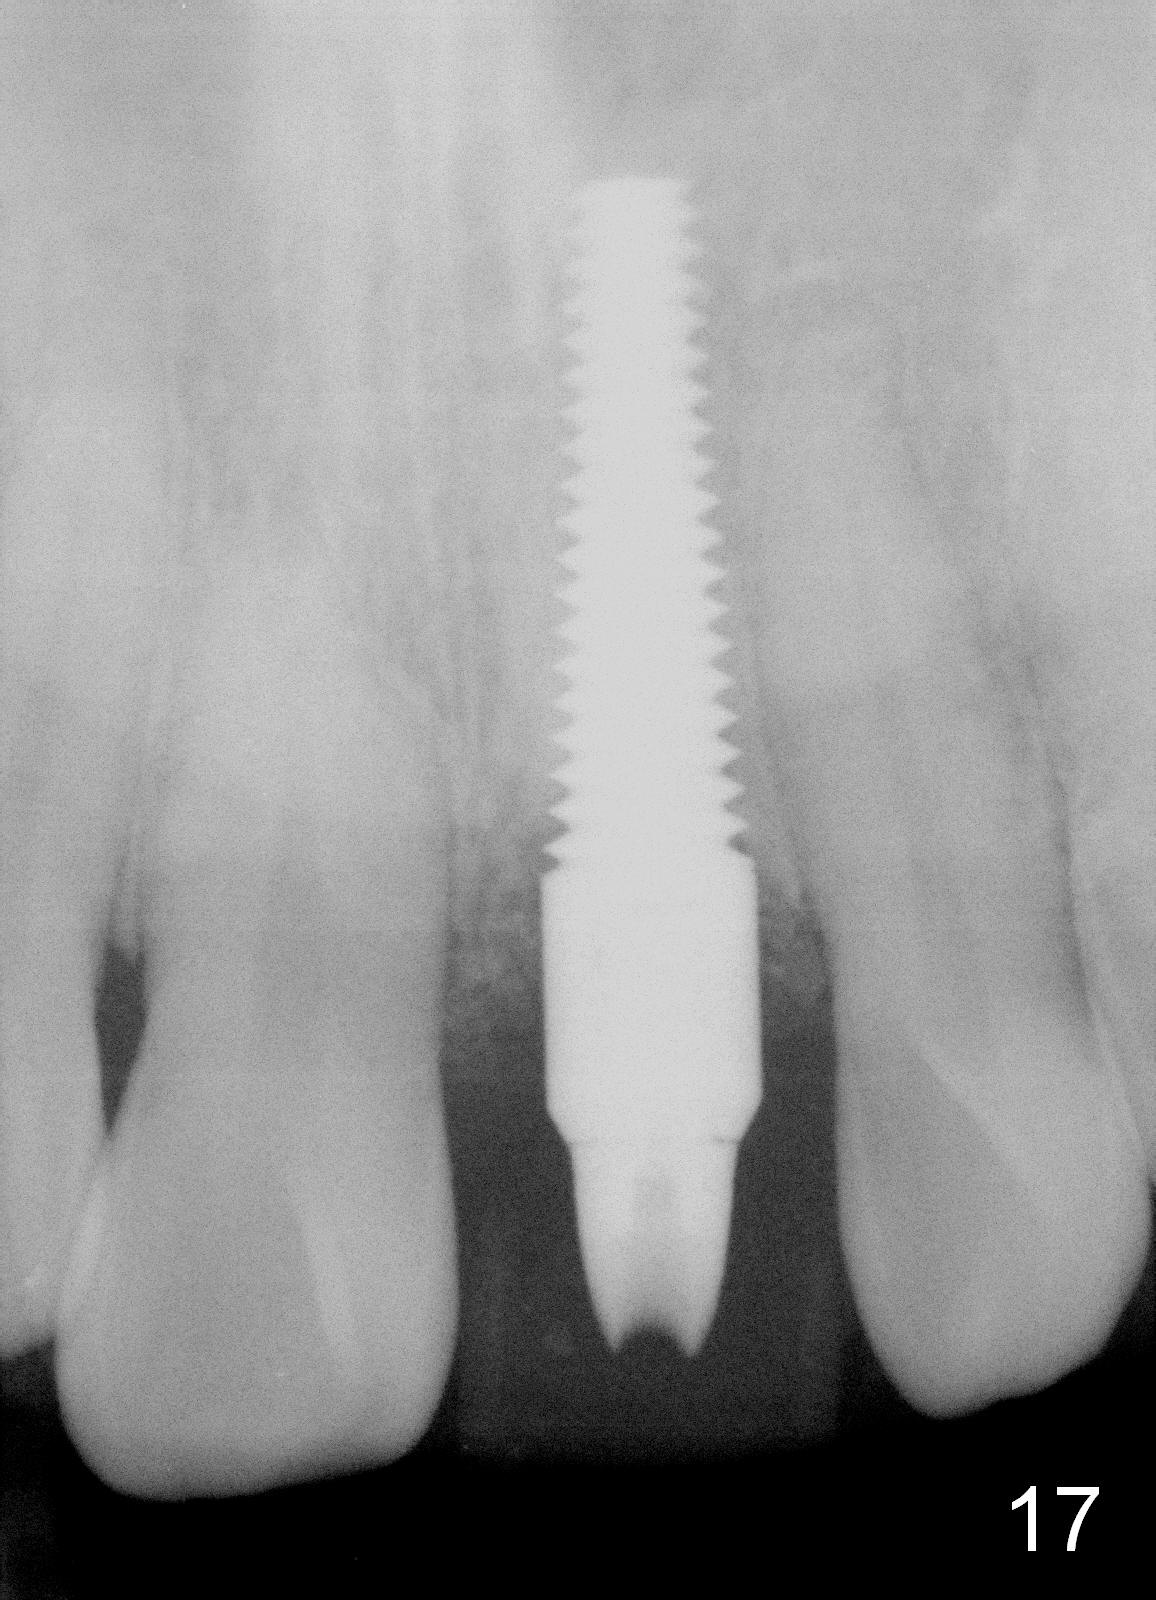

Bone expansion allows the implant (Fig.9 I) to have primary stability (insertion torque between 50 and 60 Ncm), since the cortex of the incisive canal is apparently intact. Allograft is placed in the labial gap (Fig.10, 11 *) following installation of the abutment (A). Finally an immediate provisional (Fig.10,12 P) is cemented. Fig.13,14 are taken 8 days postop. The patient returns 3 months postop (Fig.15,16). Osteointegration appears to have occurred (Fig.15 arrowheads) and is more obvious 9 months postop (Fig.17).

The permanent crown is temporarily cemented because of misshade and undercountour at the cervix (Fig.18).